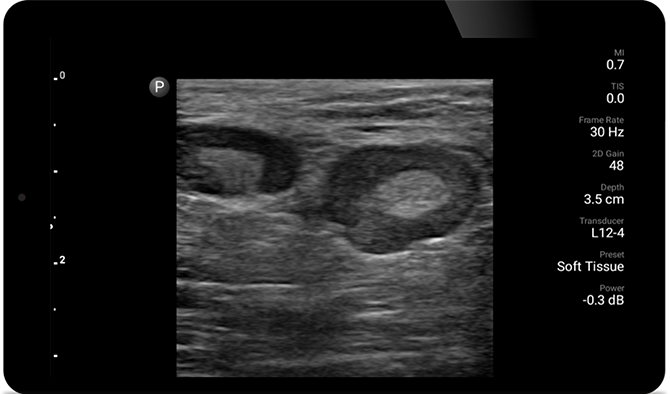

Ecografiile vă pot îmbunătăţi capacitatea de a identifica şi de a trata cu succes abcesele cutanate.

Ecografie POC pentru ţesuturile moi